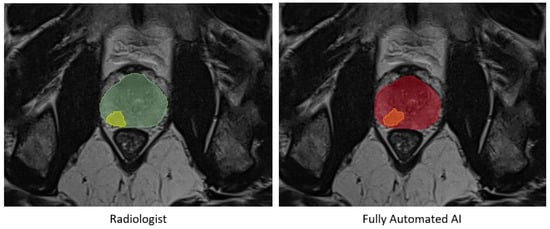

No statistically significant differences were observed in the prostate segmentation comparisons. However, in the tumor comparisons, the statistical tests on all metrics, except for precision, exhibited differences with a p-value less than 0.01 between the automated AI and AI-assisted models. Detailed results are presented in Figure 3 and Table 2 and Table 3. An example of prostate and tumor segmentation performed by a radiologist, compared to the fully automated AI method, is shown in Figure 4.

Figure 4. An example of prostate segmentation and tumor segmentation by a radiologist on the left, compared to fully automated AI method output on the right. Green: Prostate segmentation by radiologist, Yellow: Tumor segmentation by radiologist, Red: Prostate segmentation by fully automated AI, Orange: Tumor segmentation by fully automated AI.